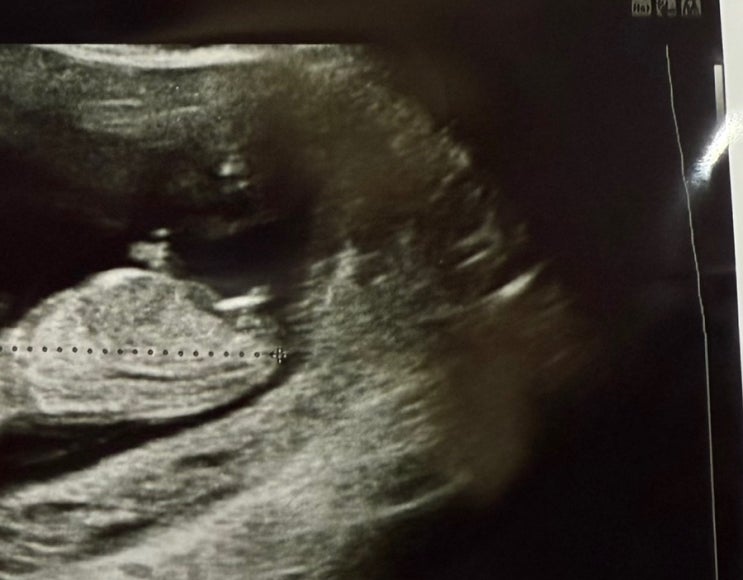

12주~16주 각도법감별사 장꾸맘님 각도법 후기

#각도법성별 #각도법후기 #장꾸맘의각도법 장꾸맘님이 성별 감별사로 유명하시대서 나도 한번 질문해봄 장...